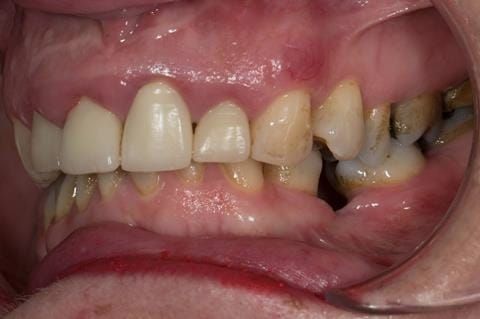

Provision of a maxillary cobalt chromium based partial denture/protective occlusal splint in a heavily restored dentition

- UR2 peri-radicular periodontitis with a peri-radicular area on the root apex. Retrograde amalgam filling from a previous apicectomy. No visible root canal or root canal filling. Large circumferential marginal gap between the crown and tooth. Large post and core present. Very little tooth structure remaining resulting in a fragile tooth with increased potential for fracture.

- UR1 peri-radicular periodontitis with a small peri-radicular area on the root apex with wide blunderbuss apex. Radio-opaque root canal filling present approximately 3 mm short of the radiographic apex. Large circumferential marginal gap between the crown and tooth. Large post and core present. Very little tooth structure remaining resulting in a fragile tooth with increased potential for fracture.

- UL1 peri-radicular periodontitis with a peri-radicular area on the root apex. Retrograde amalgam filling from a previous apicectomy. Visible root canal space with no sign of root canal filling. Large circumferential marginal gap between the crown and tooth. Large post and core present. Very little tooth structure remaining resulting in a fragile tooth with increased potential for fracture.

- UL2 peri-radicular periodontitis with a peri-radicular area on the root apex. No visible root canal or root canal filling. Large circumferential marginal gap between the crown and tooth. Large post and core present. Very little tooth structure remaining resulting in a fragile tooth with increased potential for fracture.

- High smile line showing gum above gingival zeniths of upper front teeth when smiling. Aesthetic failure of the upper four incisors with inflammation of the gingivae and mis-match of the gingival zenith levels.

- Other than the maxillary incisors the remaining dentition was in marginally better condition being moderately to heavily restored. Many will probably require replacement and restoration from time to time mainly from wear and tear owing to occlusal forces.

Following consultation and second discussion appointment the patient chose to have option 3 namely, a maxillary cobalt chromium based partial denture/protective occlusal splint. The clinical situation and treatment process is shown in detail below with photographs. The patient was successfully rehabilitated with this and her quality of life considerably improved. The clinical work was provided by Finlay and the technical work by Rowan.